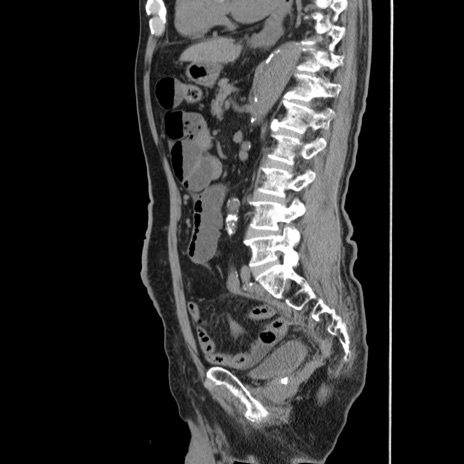

横断像

【症例】80歳代男性

【主訴】左側腹部痛、嘔吐

【現病歴】本日早朝より左腹部に痛みあり。昼頃嘔吐認めたため、救急要請。

【既往歴】直腸癌(Mile手術)、胆摘

【身体所見】意識清明、BT 35.9℃、BP 221/93mmHg、SpO2 97%(RA) 、腹部:左ストーマ周囲に限局性の腹部膨隆あり。 膨隆部自発痛・圧痛あり・軟。

【データ】WBC 7700、CRP 0.09